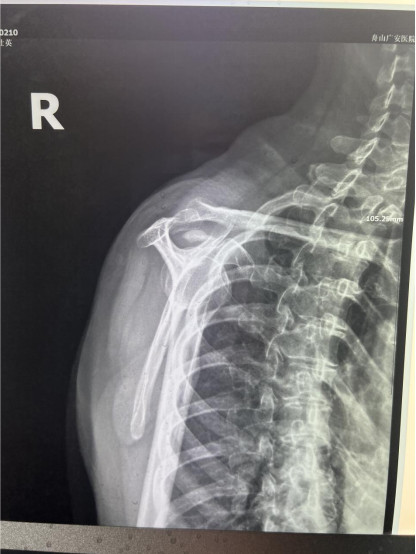

賀大媽慕名來(lái)廣安醫(yī)院找羅軍主任就診,面對(duì)羅醫(yī)生,賀大媽哭訴:“羅醫(yī)生,我真想剁下自己的這只胳膊。”羅軍主任根據(jù)患者的癥狀拍片,診斷為岡上肌鈣化性肌腱炎,隨后,羅醫(yī)生為李大媽進(jìn)行了肩關(guān)節(jié)鏡微創(chuàng)手術(shù),竟從她的右肩“擠”出“牙膏”。

鈣化性肌腱炎是一種自限性疾病,就是疾病發(fā)生發(fā)展到一定程度后,經(jīng)長(zhǎng)期機(jī)體調(diào)節(jié)能夠控制病情發(fā)展并逐漸恢復(fù)痊愈。它分為四個(gè)階段:鈣化前期、鈣化形成期、鈣化吸收期、鈣化后期,往往在“鈣鹽斑塊”吸收時(shí),疼痛最劇烈,賀大媽就正處于“吸收期”。